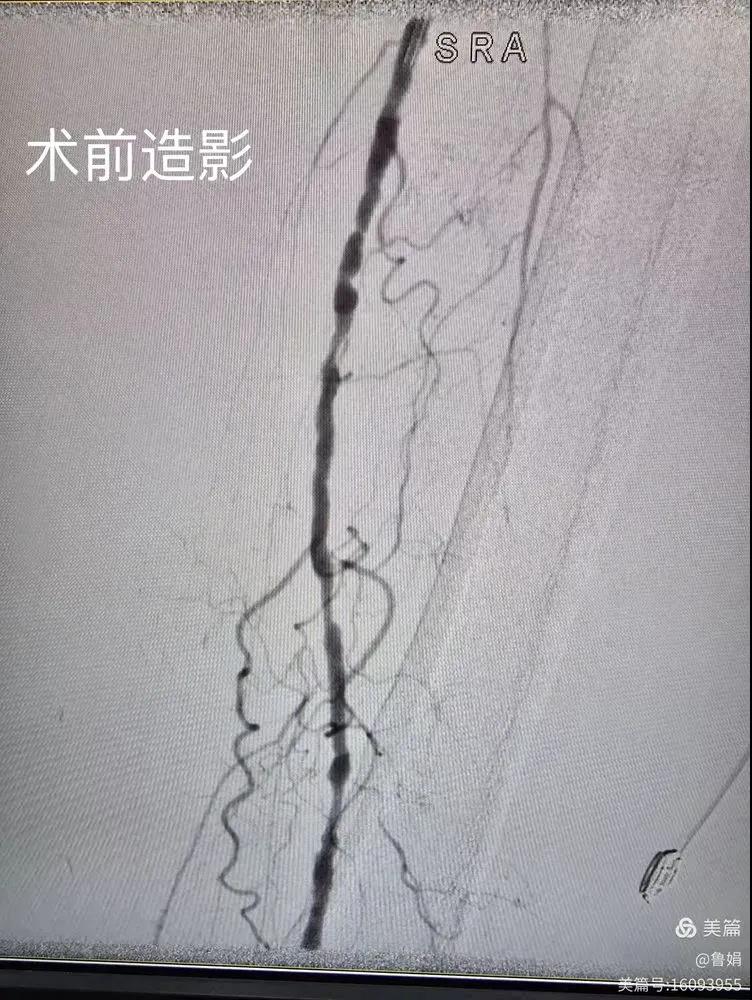

據悉,該患者,女,73歲,下肢動脈硬化閉塞癥,“以靜息痛,間歇性跛行”入院,CTA評估:股淺動脈,腘動脈間斷性多段重度狹窄,外二科血管外科團隊根據患者病情,結合檢查結果,經過科室會診后,決定對該病人行介入治療。手術由周創業副主任與北大一院血管外科專家郭宏杰教授聯合開展,對股淺動脈,腘動脈重度閉塞段行血管開通+藥涂球囊擴張成形,術后狹窄明顯緩解,血流恢復!